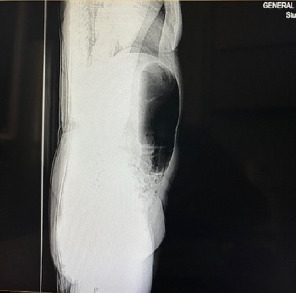

Introduction: Volvulus of the caecum, ascending colon and first third of the transverse colon is a very rare surgical emergency. Timely diagnosis and intervention can avert serious complications. Case Report: A 54-year-old woman presented to the emergency department with colicky epigastric pain radiating to the left iliac fossa that lasted for 12 h. Vital signs were stable upon arrival at the hospital. Physical examination revealed that left abdomen and suprapubic fullness and bowel sounds were recorded, and rebound tests were negative. Laboratory results were neutrophils: 78% (35%-72%), lymphocytes: 16% (20%-45%), HB: 11 g/dL (12-16), HCT: 33% (36%-48%); all the rest were normal. Furthermore, computed tomography revealed a distended close of the large bowel extending from the left hypochondrium to the left iliac fossa. During explorative laparotomy, volvulus of the first third of the transverse, ascending colon and caecum was detected. Because the viability of the bowel wall was compromised, right extended hemicolectomy was performed with consequent ileotransverse anastomosis. The postoperative period was uneventful, and the patient was discharged on the fourth postoperative day. Conclusions: Expeditious diagnosis and early intervention of very rare surgical emergencies such as ascending colon volvulus may avert disastrous complications.

Abstract Image